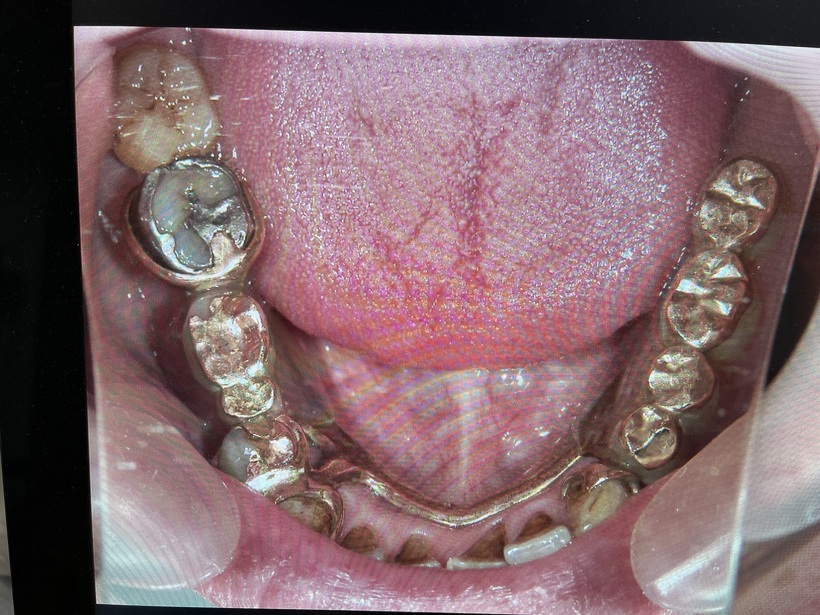

下顎義歯と残存歯

当時当院は保険診療をしていましたが患者さんに自費の義歯の作成を許可して頂きました。初診より1年半後新しい上下の部分義歯が完成しました。最高の金属(白金加金)を使用したため上下で70万円になりました。支払い時患者さんは「高いな~!」と思われたそうです。義歯装着より25年余りが過ぎ多少の修理はあったもののそのままの義歯を快適に使用出来ています。最近の感想は「こんなにも安い買い物は他になかった‼」です。